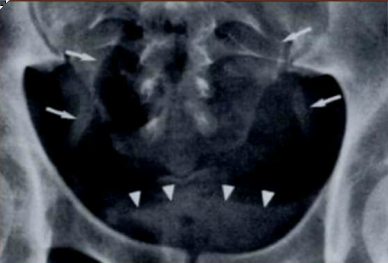

What sign is this?

Cupola sign, the patient is laying down and you see air below the hemidiaphragm

Pneumobilia, common bile duct filled with air leading to air seen in center of liver, this is often from surgery, air from duodenum enters biliary tract, benign condition.

What is this condition associated with?

Portal venous gas is associated with ischemic bowel. Air seen in periphery of liver.